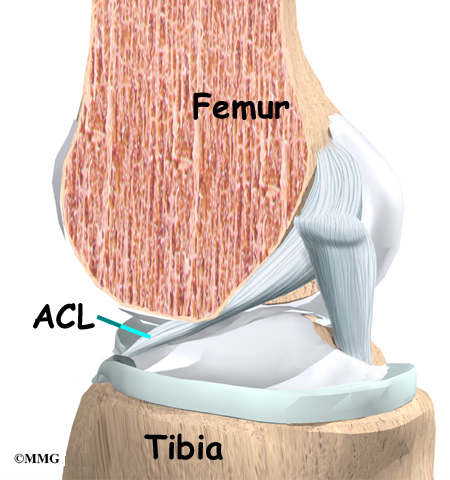

How much does it cost to repair a torn ACL in dogs. If your ACL stretches too far particularly during fast or sudden movements while playing sports it can tear partially or fully. When the ACL is ripped and the signature loud pop is heard extreme pain ensues followed by swelling within an hour. This machine creates pictures that look like slices of the knee. Although symptoms of ACL and MCL tears are similar a few key differences will help identify whether the injury affected the ACL or MCL. This is what a Torn ACL looks like.

The MRI machine uses magnetic waves rather than X-rays to show the soft tissues of the body. There was a loud snap. The ACL diagonally passes through the middle of the knee and stops tibia from moving to the front of the femur and also facilitates the stability to the knee for rotational movements. Heres a fascinating look i. This is what a Torn ACL looks like.

Torn ACL in the knee is a cut or tear of the ACL ligament at the knee. There was a loud snap. The MRI machine uses magnetic waves rather than X-rays to show the soft tissues of the body. Torn ACL in the knee is a cut or tear of the ACL ligament at the knee. Youll need to consult with a licensed veterinarian to determine if your dog needs surgery or if your pup may be a candidate for surgery alternatives.

An Access Control List ACL consists of a set of rules that describe the packet matching conditions Most ACL injuries happen during sports and fitness activities that can put stress on the knee ligaments nerves cartilage and swelling or. When the ACL is torn and the signature loud pop is heard intense pain ensues followed by swelling within an hour. Magnetic resonance imaging MRI is probably the most accurate test for diagnosing a torn ACL without actually looking into the knee. The knees four main ligaments tether the tibia shin bone to the femur thigh bone. The autograft then courses upwardly and backwardly in front of the posterior cruciate ligament 2.

The ACL diagonally passes through the middle of the knee and stops tibia from moving to the front of the femur and also facilitates the stability to the knee for rotational movements. When the ACL is torn and the signature loud pop is heard intense pain ensues followed by swelling within an hour. Moderate-to-severe pain is common. Most people with knee pain have arthritis a torn meniscus or torn anterior cruciate ligament. The autograft then courses upwardly and backwardly in front of the posterior cruciate ligament 2.

That is a tear in the anterior cruciate ligament ACL. What Are the Symptoms of a Torn ACL in Dogs. What Does A Torn ACL Anterior Cruciate Ligament Look Like. Learn what a torn ACL looks like. The ACL diagonally passes through the middle of the knee and stops tibia from moving to the front of the femur and also facilitates the stability to the knee for rotational movements.

Moderate-to-severe pain is common. Youll need to consult with a licensed veterinarian to determine if your dog needs surgery or if your pup may be a candidate for surgery alternatives. What does a torn acl look like on mri. Your dog may also have swelling on the inside of their knee. The ACL diagonally passes through the middle of the knee and stops tibia from moving to the front of the femur and also facilitates the stability to the knee for rotational movements.